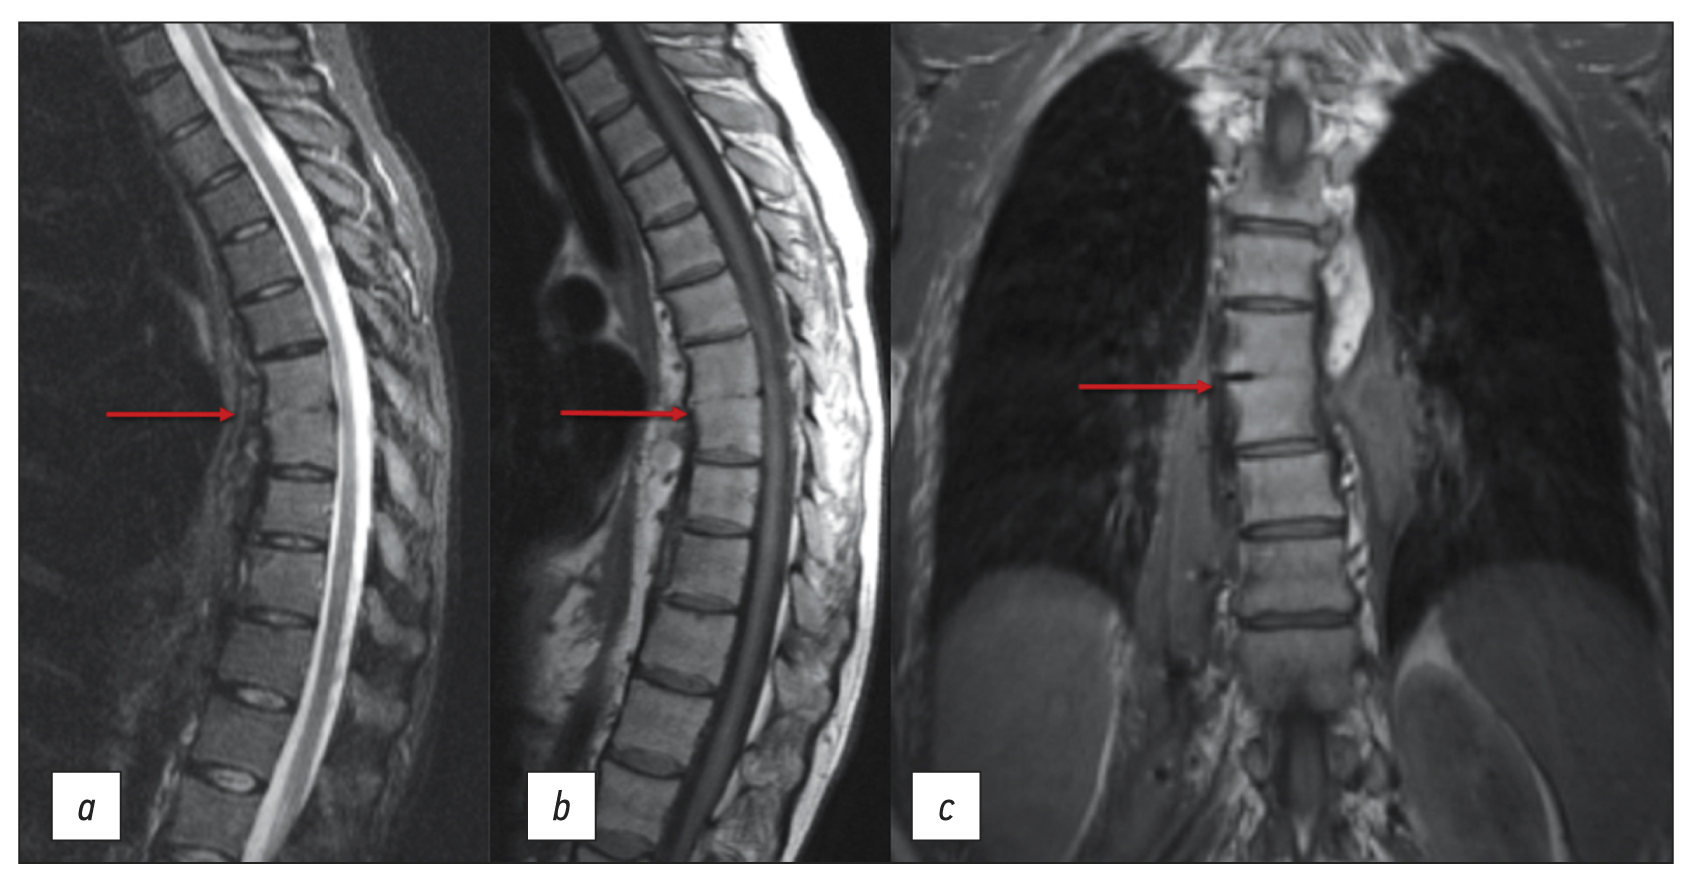

Chronic esophageal fistula as a rare cause of secondary osteomyelitis of the thoracic spine

Resumo

Infectious diseases affecting the spine are inflammatory destructive diseases that involved the organ and its structural elements as a result of infection by hematogenic, lymphogenic, or contact pathways, including may be a complication of surgical intervention. In arriving at an accurate diagnosis, it is extremely important to evaluate the anamnesis, the clinical picture, as well as the data of laboratory studies and radiation diagnostics in the aggregate.

This article presents a clinical case with the development of secondary ThVII–ThVIII vertebral spondylitis due to esophageal fistula. At the initial diagnosis, spondylitis was associated with spinal anesthesia performed six months prior to onset of the disease, as there was a fistulous defect on the skin in the lumbar region. Consequently, surgical interventions were performed three times in a surgical hospital at the place of residence. The data from the endoscopic examination, as well as the patient’s complaints regarding the relationship between meals, the appearance of pain, and the nature of the discharge from the fistula were not taken into account by doctors initially. With the help of an additional examination, including computed tomography of the esophagus with oral contrast and computed tomography fistulography, the main diagnosis was esophageal fistula. Thoracic spondylitis was only a secondary complication.

Thus, the final diagnosis of back pain and fistula in the lumbar region should be formulated after differential diagnosis with alternative diseases of the spine.